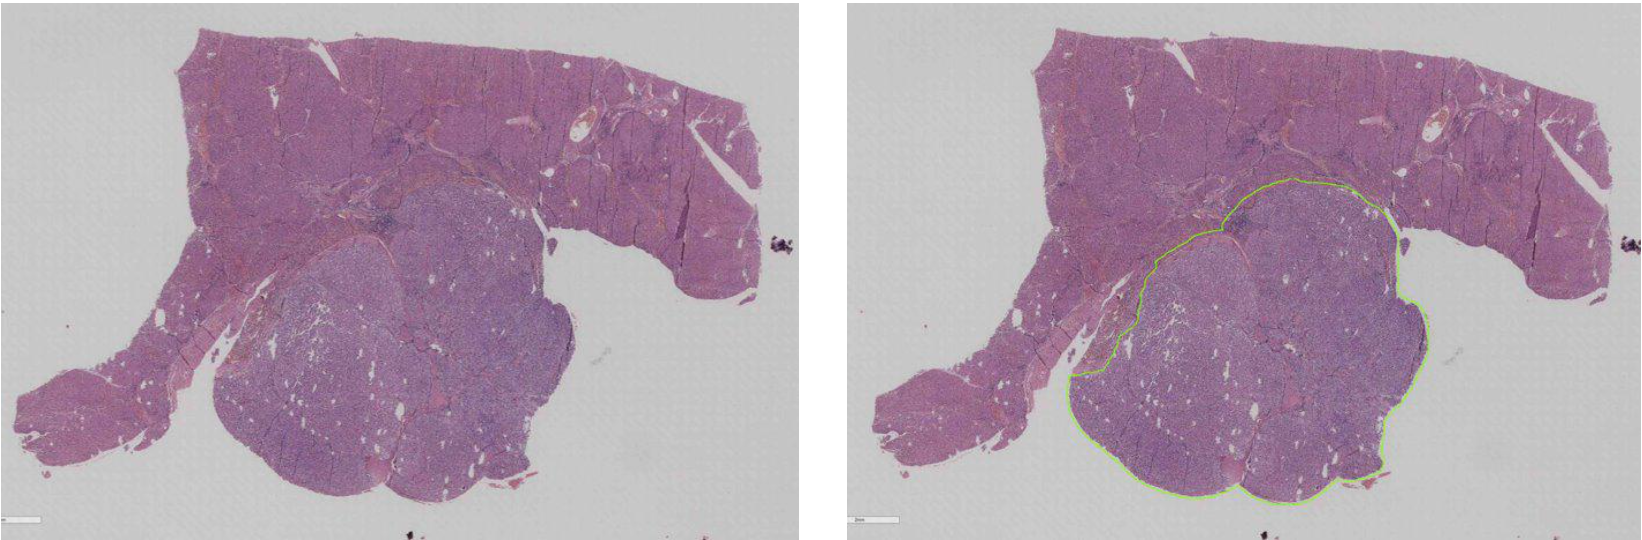

肝癌预后

该合作重点探索基于肝脏WSI切片的肝癌复发模式。

武汉同济医院